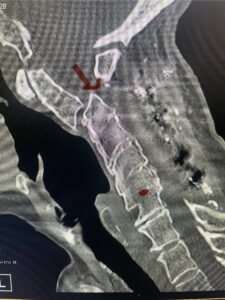

Fig. 6a: Sagittal cervical CT scan demonstrating an abnormally thin right C2 isthmus prohibiting safe placement of screw (red arrow). Notice the vertebral foramen eroding the isthmus bone structure (red dot).